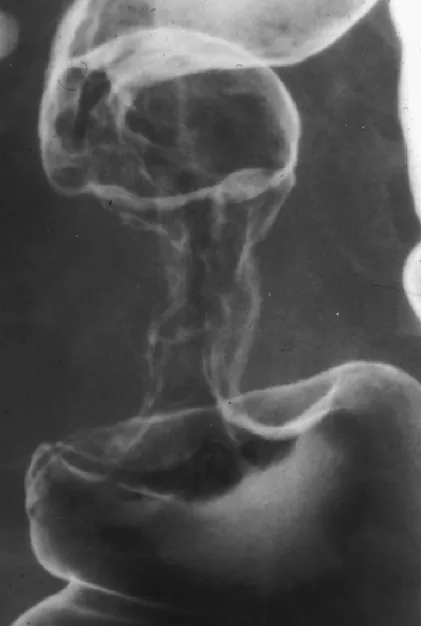

Hình 2: Minh hoạ chụp niệu đồ tĩnh mạch để đánh giá hệ tiết niệu.

Nguồn: trung tâm y khoa Deep medical centre